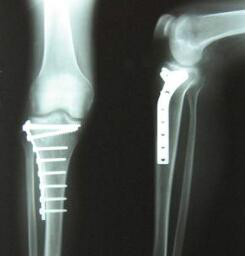

国家对骨科的相关规定

根据国家卫计委颁布的《医疗机构基本标准(试行)》三级综合医院,二级中医医院、三级中医医院、二级中西医结合医院、三级中西医结合医院、三级口腔医院等设有骨科科室。 二级医院骨科服务能力标准 (1)必…

骨科基本介绍

骨科是各大医院最常见的科室之一,主要研究骨骼肌肉系统的解剖、生理与病理,运用药物、手术及物理方法保持和发展这一系统的正常形态与功能。随着时代和社会的变更,骨科伤病谱有了明显的变化,例如,骨关节结核、骨髓…